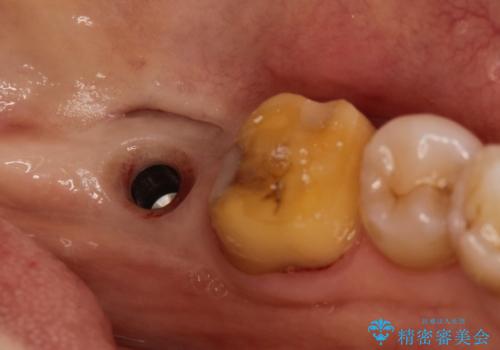

- 左下の1番後方の歯が欠損しており、インプラントにて咬合回復する計画としました。

レントゲン・CT撮影により骨の高さがあまりないことがわかり、ショートインプラントを選択しました。

また、清掃性を確保するために歯肉の移植も行うこととしました。